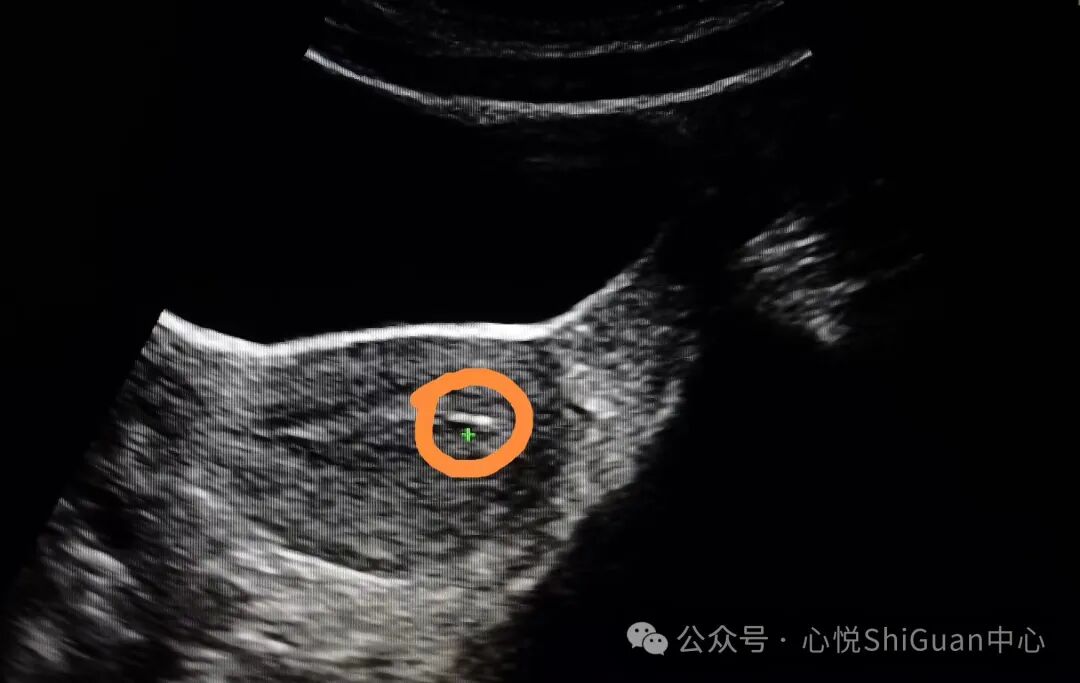

1、取卵过多易发生OHSS

卵巢过度刺激综合征(OHSS)是一种人体对促排卵药物产生的过度反应的并发症。

主要临床表现为卵巢囊性增大、毛细血管通透性增加、体液积聚于组织间隙,引起腹腔积液、胸腔积液,伴局部或全身水肿等,这种并发症不但会影响到患者的身体健康,还会阻碍试管进程。

所以一般认为,取卵数量在5~15个之间是比较理想的。